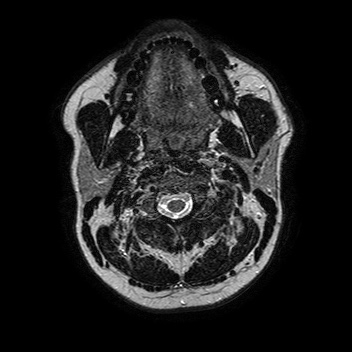

Плоскоклеточный Рак Полости Рта Фото

Плоскоклеточный Рак Полости Рта Фото 115 фотографий